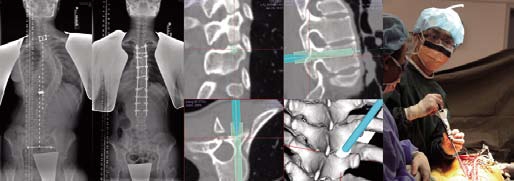

Adolescent Idiopathic scoliosis corrective surgery with use of computer navigation

Lower Limb Deformity Correction using Taylor Spatial Frame |